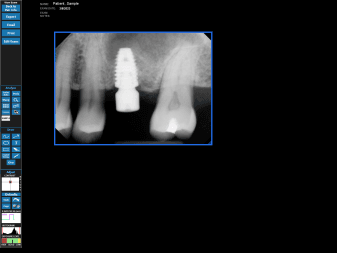

Digital X-Rays

XDR Digital X-Rays